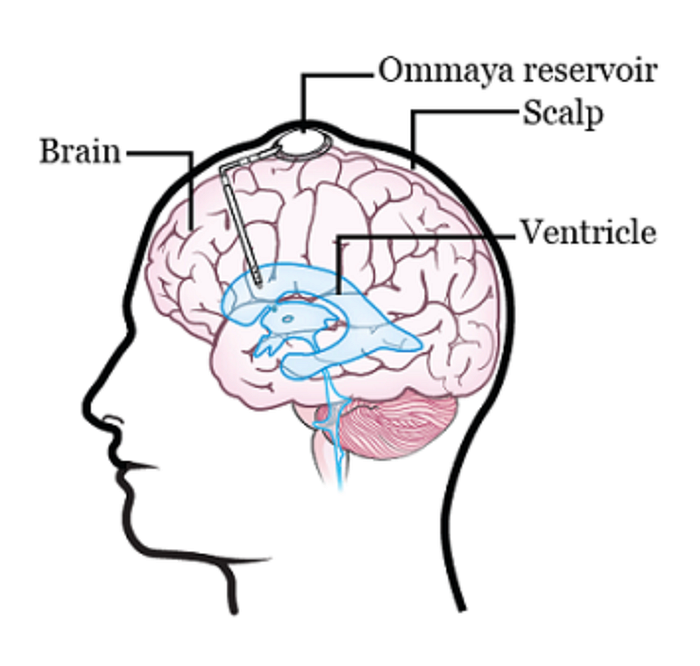

There are two different ways to do this. One way is to inject the drugs into an Ommaya reservoir (a dome-shaped container that is placed under the scalp during surgery; it holds the drugs as they flow through a small tube into the brain). The other way is to inject the drugs directly into the cerebrospinal fluid (CSF) in the lower part of the spine.

The main issue with the Ommaya reservoir is that surgery is required to both implant and remove the reservoir itself, raising the likelihood of getting an infection or other side effects. Furthermore, you are limited in your activities as you can’t do anything that would risk damaging the reservoir (e.g. contact sports) and you must be constantly wary about hitting your head. Here is a breakdown of all of the risks involved with this procedure:

- There is a small risk that you could bleed into your brain.

- There is a small risk that you could have some loss of function.

- There is a small risk that you could get an infection in your brain.

- The Ommaya reservoir may need to be adjusted. To make sure it’s in the right place, you will get a computed tomography (CT) scan the day after your surgery. If your reservoir isn’t in the right place, you may need to undergo another surgery to correct it.

- The Ommaya reservoir may fail. To make sure your Ommaya reservoir is working, a CSF flow study may be done after your surgery.